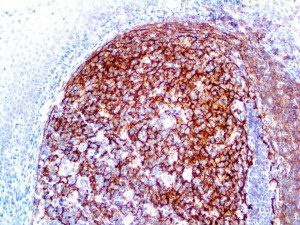

It is the ICU physician who is most likely to witness one of the deadliest manifestations of the abnormal immunological response, the cytokine storm syndrome (CSS). This response is also referred to by some as the cytokine release syndrome (CRS). CSS is characterized by continuous activation and expansion of macrophage and lymphocyte populations, which secrete large amounts of cytokines, causing the cytokine storm. This massive cytokine release is akin to hemophagocytic lymphohistiocytosis (HLH) disease, a syndrome characterized by initial unchecked and persistent activation of cytotoxic T lymphocytes and NK cells.

Clinical and laboratory manifestations of HLH include fever, enlarged liver and/or spleen, neurologic dysfunction, coagulopathy, liver dysfunction, cytopenias (i.e., low levels of erythrocytes, leukocytes, and/or platelets), hypertriglyceridemia, hyperferritinemia, hemophagocytosis, and eventually diminished NK cell activity as the immune system becomes progressively paralyzed. HLH can be familial (primary HLH) or secondary to another disease process (sHLH), such as rheumatic disease, in which it is referred to as macrophage activation syndrome (MAS, characterized by elevated ferritin).